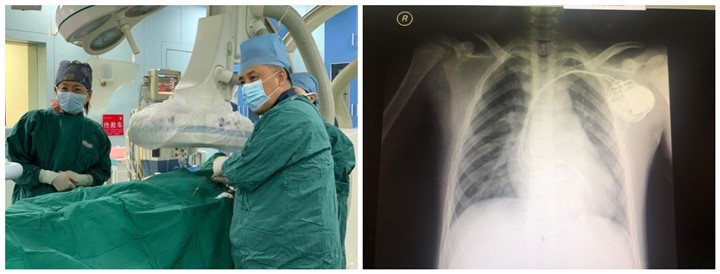

2020年1月21日14:30,复旦大学附属儿科医院心内科成功为一名12岁男童实施了心内膜心脏起搏器的植入手术。患儿3个月前偶然发现心率慢,入院前1周晕厥多次,无法继续上学。心电图及24小时Holter检查均显示Ⅲ度房室传导阻滞,频繁出现大于5秒心室停博,有猝死风险。在对患儿进行充分评估后,21号下午,心内科刘芳主任与何岚医生,在复旦大学附属中山医院心内科宿燕岗教授指导下,经左锁骨下静脉顺利植入双腔心脏起搏器,整个手术过程历时仅半个小时。

心脏起搏器是一种将电池提供的电刺激通过导线传递到与心脏接触的电极的装置,主要用来治疗心动过缓。心动过缓是儿童和成人最常见和没有争议的永久性起搏器植入指征,如心率小于40次/分或停搏大于3秒,同时伴随一些症状如晕厥,为安装起搏器的主要指征。多数先天性心脏传导阻滞患儿最终都需要安装起搏器。既往,儿童更常采用开胸心外膜起搏,随着技术改进,起搏发生器和电极变得更小、更先进,小年龄患儿也可经静脉植入起搏器。经静脉植入的心内膜起搏器除了手术创伤较小外,心房和心室夺获阈值普遍较低,起搏问题明显减少,起搏器寿命可延长至13-15年。双腔起搏能够模拟正常人的心房-心室顺序起搏,保护孩子的心脏功能,出院后患儿可逐渐恢复正常学习和运动。